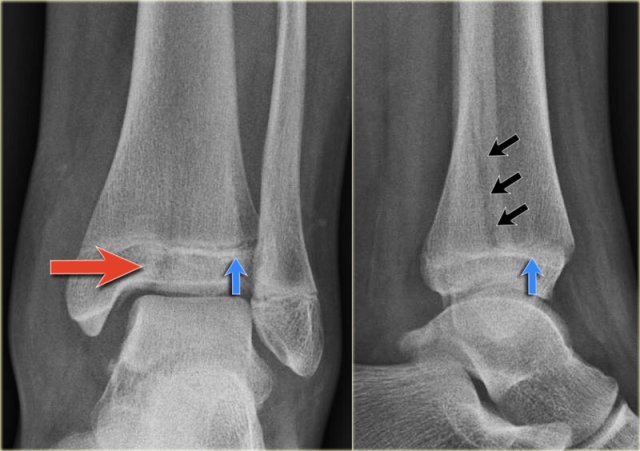

Study the images and then scroll to the next images.

The fracture through the epiphysis can be easily missed (blue arrow).

The fracture through the growth plate is only seen on CT.

Continue with the CT images.

The CT-images nicely display the fracture through the growth plate and the epiphysis.

This is also a Salter-Harris type III fracture.

Notice that there is also a Tillaux fracture.

We will discuss these fractures in a moment.